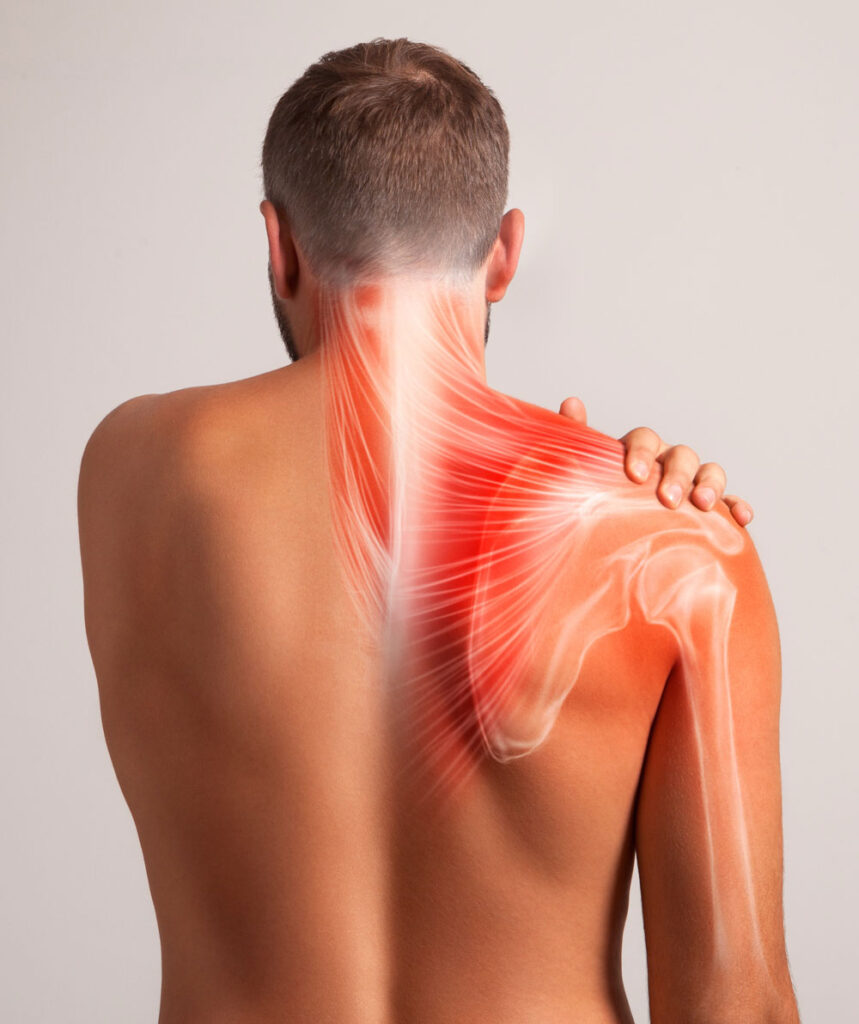

Shoulder Pain

The shoulder is the most complex joint in the human body. It has to move through more than 180 degrees of motion in many directions, rotate, slide and spin. There are a variety of muscles that have to work in concert to ensure the shoulder joint tracks properly with everyday activities. It is made up of the humerus bone, scapula (shoulder blade) and clavicle (collar bone). There are technically 4 joints that make up the entire shoulder complex.

Poor posture, weakened muscles, injury and lack of proper range of motion can all factor into shoulder pain. Shoulder pain is typically felt in the muscles between the shoulder and neck, as well as the outside shoulder radiating down. Where your pain is can determine what structures are involved.

It is important to note that just because your pain is felt in one location, that is not usually the source of the trouble. For example pain on the outside of the shoulder can be from an impingement of the joint or problems with the rotator cuff muscles. However, this can be caused by poor positioning and functioning of the shoulder blade, which is the real culprit. Treat the source of the problem and the irritation will resolve.